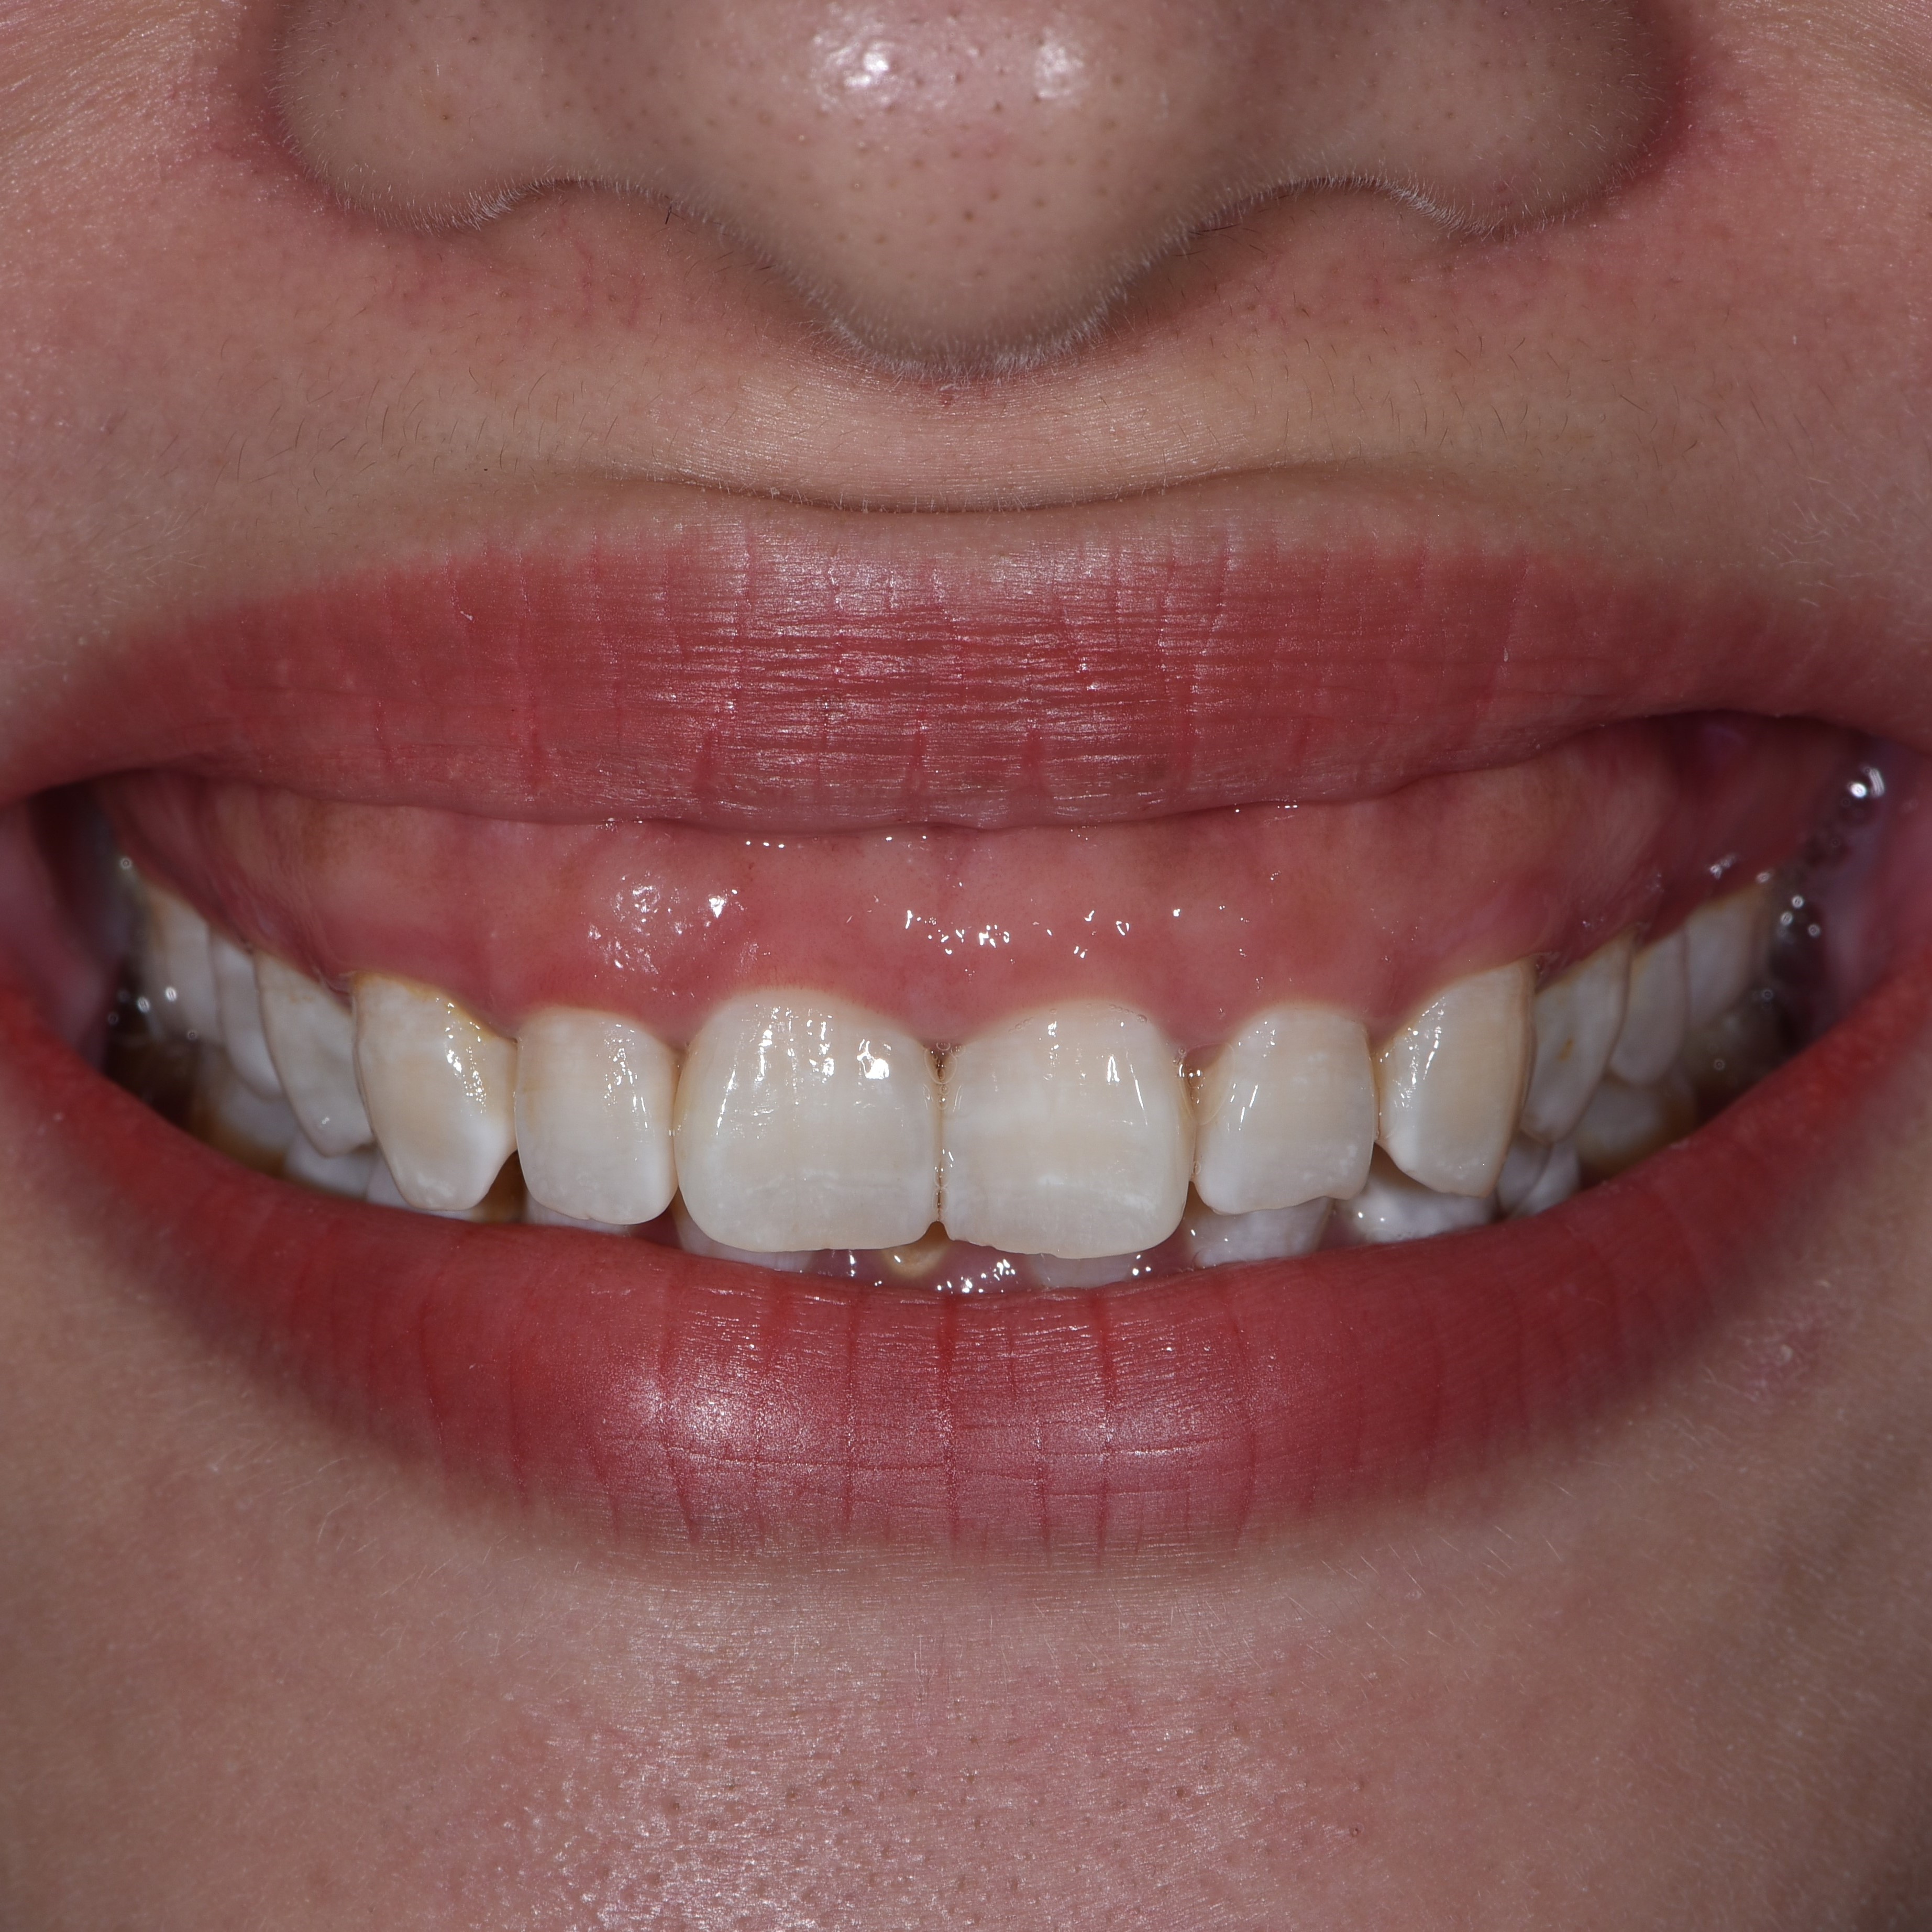

Cười hở nướu

Tình trạng cười hở lợi có thể được điều chỉnh bằng các kỹ thuật thẩm mỹ nha khoa, mang lại nụ cười tự nhiên và tự tin hơn